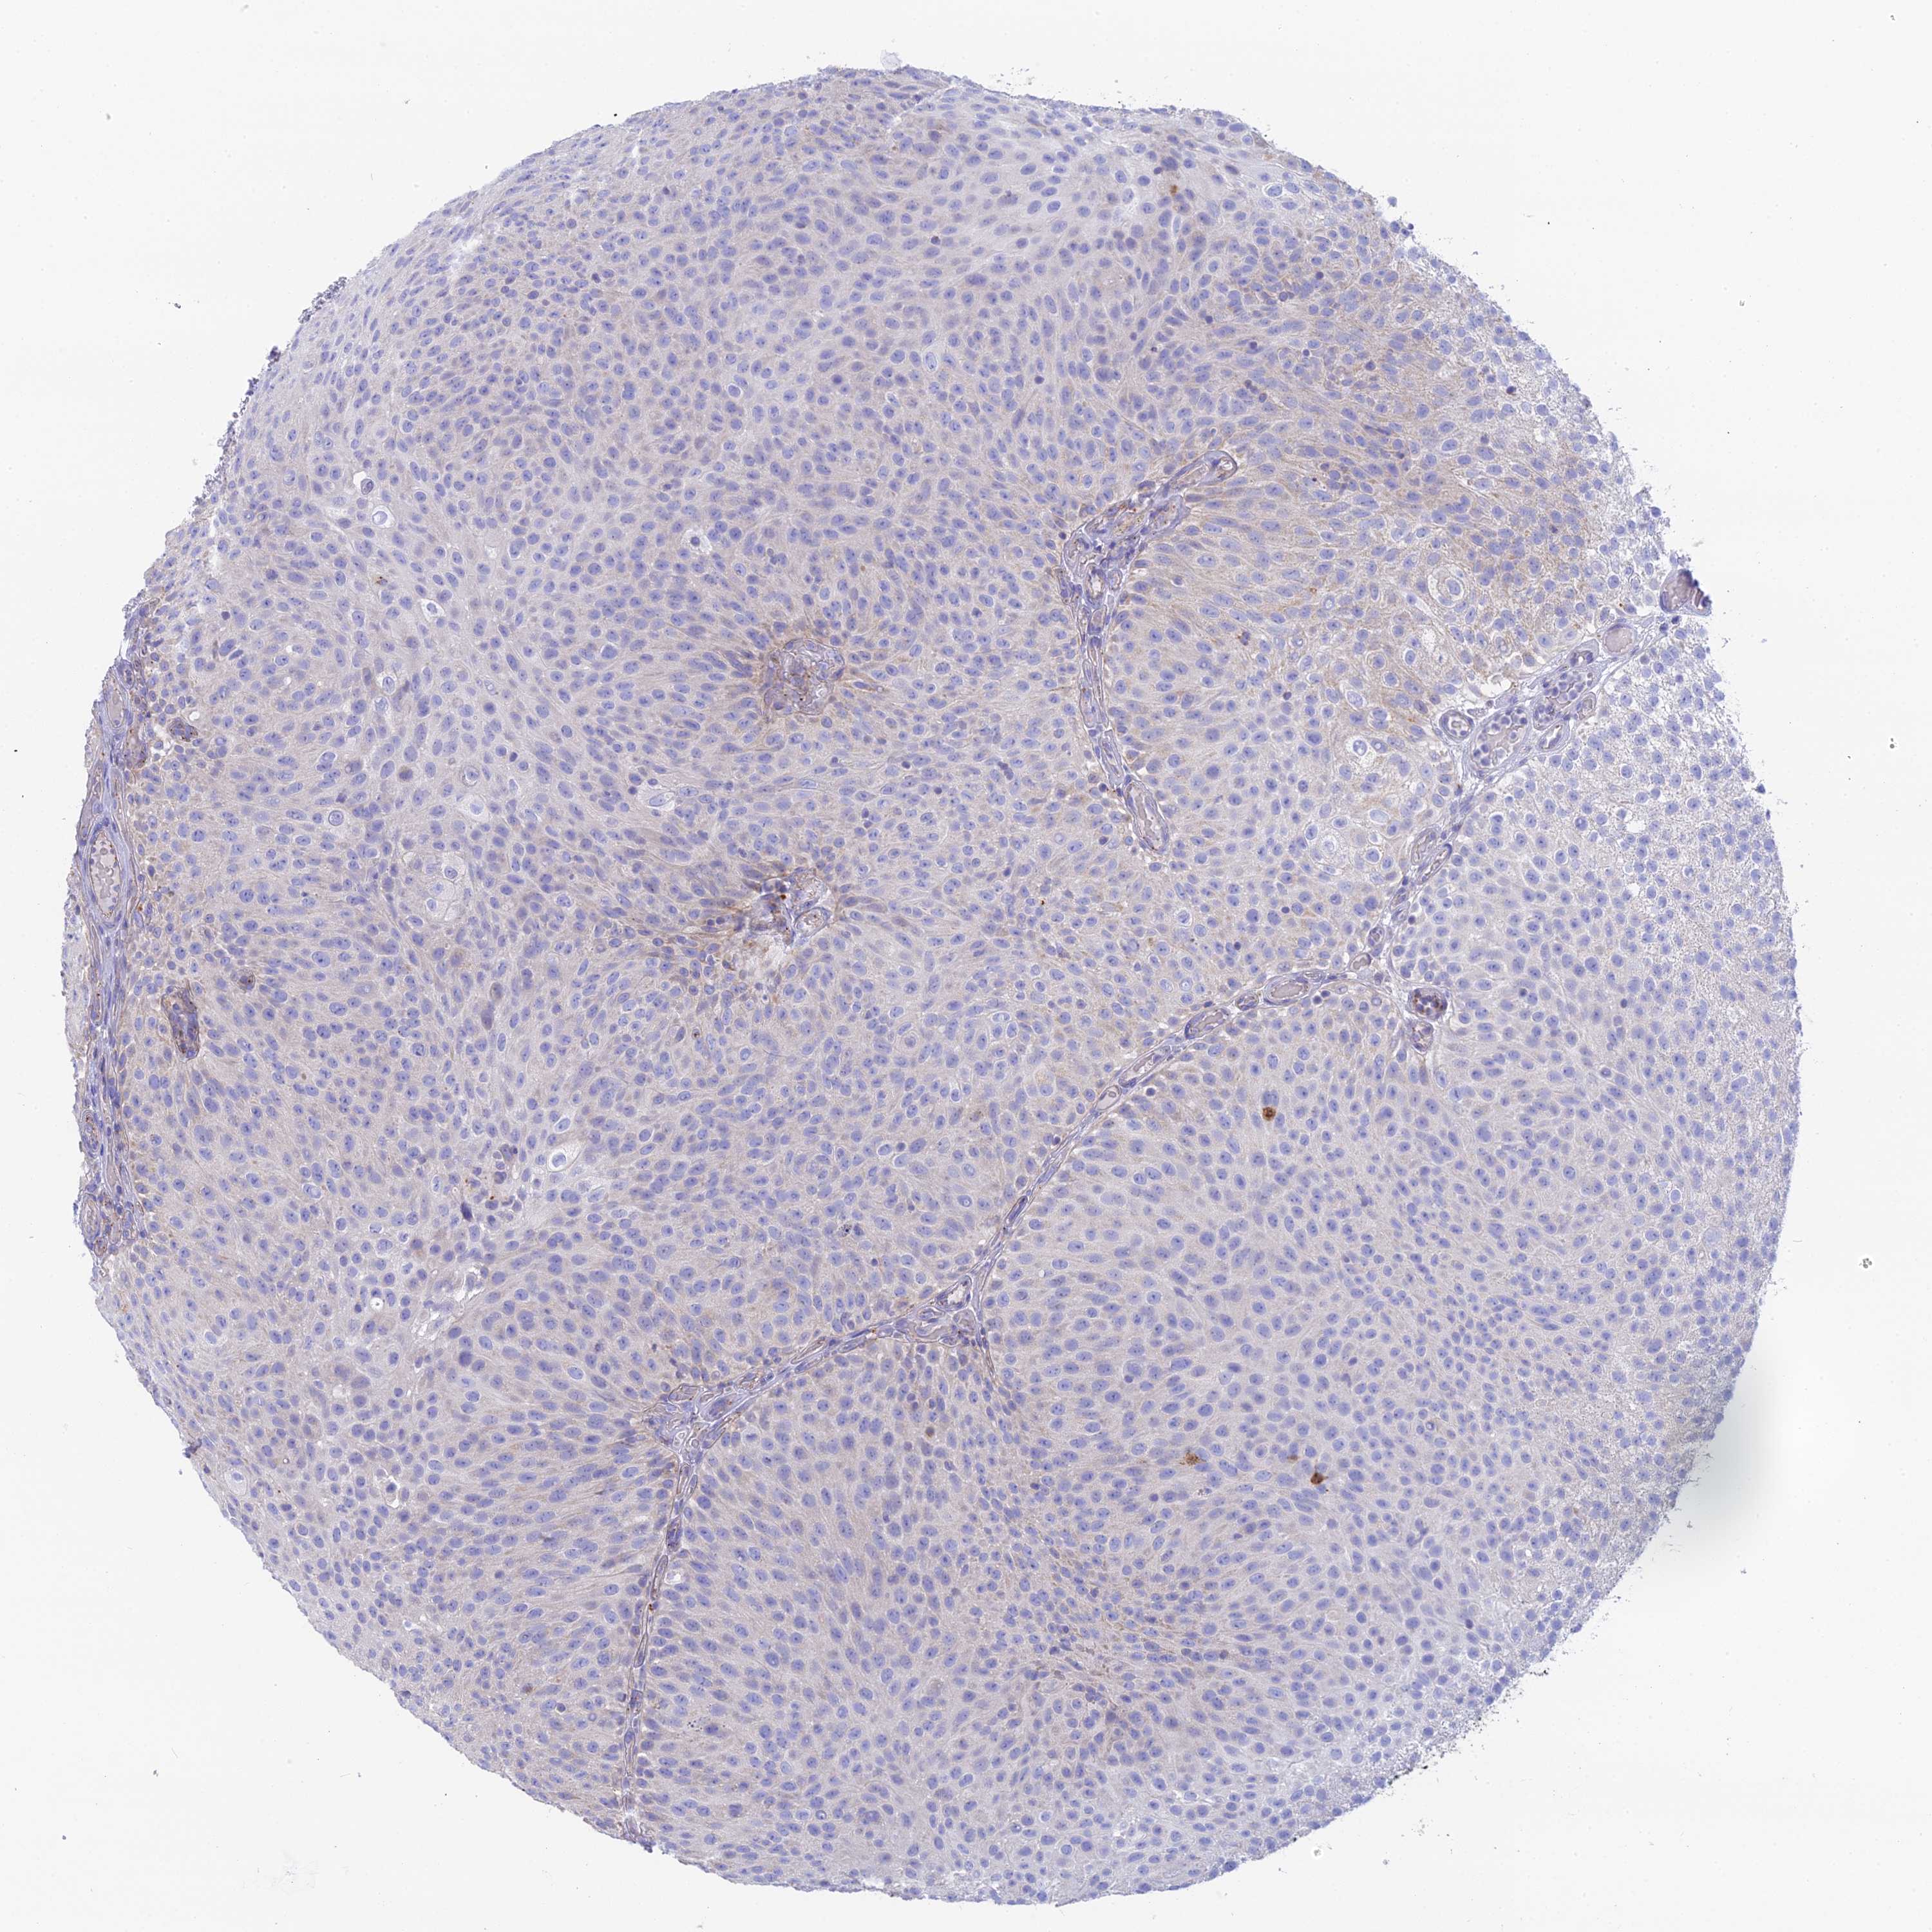

UROTHELIAL CANCER - Protein expressioni

A mouse-over function shows sample information and annotation data. Click on an image to view it in a full screen mode. Samples can be filtered based on level of antibody staining by selecting one or several of the following categories: high, medium, low and not detected. The assay and annotation is described here.

Note that samples used for immunohistochemistry by the Human Protein Atlas do not correspond to samples in the TCGA dataset.

Antibody stainingi

Antibody staining in the annotated cell types in the current human tissue is reported as not detected, low, medium, or high, based on conventional immunohistochemistry profiling in selected tissues. This score is based on the combination of the staining intensity and fraction of stained cells.

Each image is clickable and will lead to virtual microscopy that enables deeper exploration of all samples and also displays staining intensity scores, fraction scores and subcellular localization as well as patient and tissue information for each sample.

Antibody HPA042622

Staining

High

Medium

Low

Not detected

Intensity

Strong

Moderate

Weak

Negative

Quantity

>75%

75%-25%

<25%

None

Location

Urothelial carcinoma, High grade

Urothelial carcinoma, Low grade